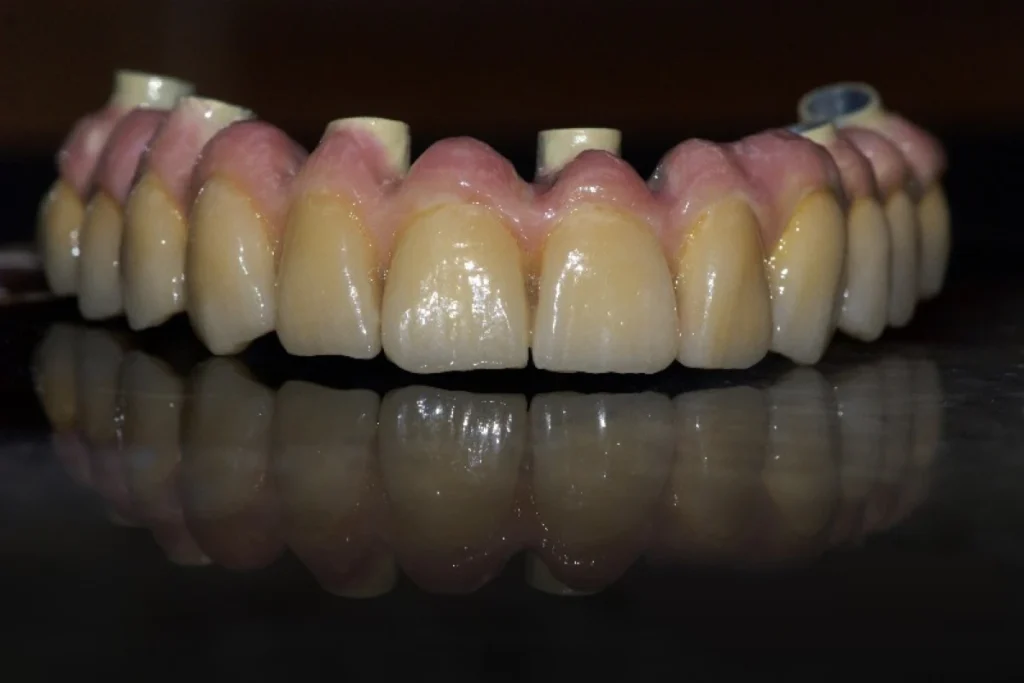

2. Les bridges dentaires fixes

Le bridge est une prothèse fixe qui permet de remplacer une ou plusieurs dents manquantes en s’appuyant sur les dents voisines. Ces dents, appelées dents piliers, servent de support pour maintenir la restauration.

Le bridge peut être réalisé en zircone, en céramique ou en alliage métallique. Chaque choix est dicté par les besoins cliniques et les attentes esthétiques.

La prothèse conjointe ne se limite pas à restaurer la fonction masticatoire. Elle contribue aussi fortement à l’esthétique et au bien-être psychologique. Retrouver un sourire harmonieux redonne confiance au patient, tant dans sa vie personnelle que professionnelle.

Nous attachons donc une attention particulière à l’intégration esthétique de chaque prothèse. La forme, la teinte et la translucidité sont soigneusement étudiées pour s’harmoniser avec les dents naturelles et offrir un rendu discret et naturel.